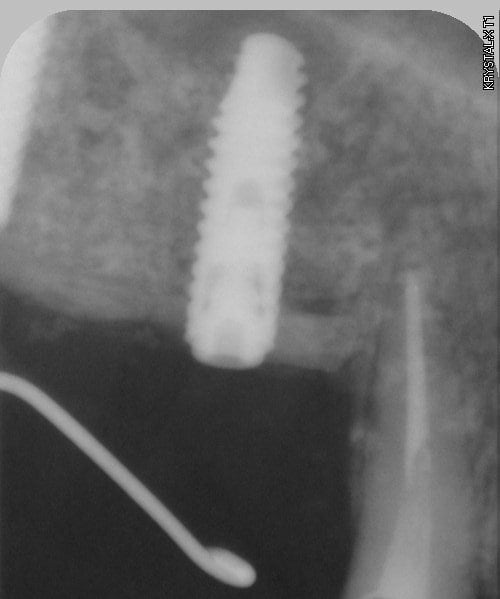

bon et bien ça c'est fait!

curetage (deux bonnes heures) dépose des deux vis d'ostéo et de l'implant en 16, nettoyage implant en 14/15 (axe un peu limite pour cause structure osseuse) et 17.

Vitalos

on croise les doigts.

photos montrant le hiatus greffe/os et pose avec vitalos à la fin